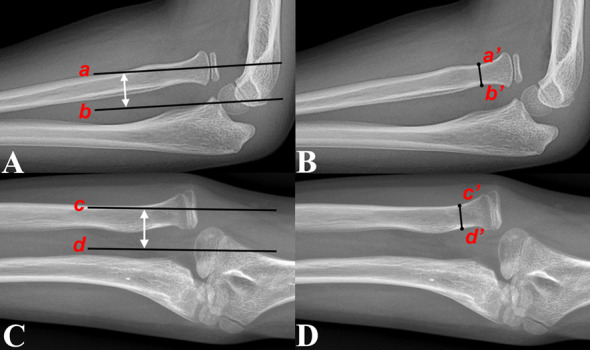

Materials and methods: We retrospectively reviewed 274 patients (mean age at injury: 5.82 ± 2.62 years) with UCMFs with all types of anterior (group A) and non-anterior (group B) radial head (RH) dislocations. Radiographs were used to assess the presence, size and bone density of HO. The risk factors evaluated included age at injury, sex, laterality, interval from injury to diagnosis, presence of radial or median nerve injury, immobilization of the fractured ulna after injury, direction of RH dislocation and distance of RH dislocation (DD-RH). The results were compared with 76 patient demographics-matched paediatric acute Monteggia fractures (PAMFs) undergoing surgery within 48 h after injury.

Results: The HO rate (13.1%) in children with UCMFs was significantly higher than that (0%) in children with PAMFs (P = 0.001). The incidence of HO (14.5%) in group A was significantly higher than that (0%) in group B (P = 0.032). Age at injury and DD-RH were confirmed as risk factors for HO in patients with UCMFs by both univariate and logistic regression analyses (P < 0.05). Receiver operating characteristic curve analysis and chi-squared analysis indicated that age at injury > 6.78 years and DD-RH < 1.59-fold of the narrowest radial neck width were the cut-off values for an increased HO rate in patients with UCMFs (P < 0.05). Increased age at injury (P = 0.041) and interval from injury to diagnosis (P = 0.006) were associated with high-bone density HO.

Conclusions: Patients with UCMFs with anterior RH dislocations, age at injury > 6.78 years, and DD-RH < 1.59-fold of the narrowest radial neck width were more likely to develop HO. The bone density of HO increases with age at injury and interval from injury to diagnosis. Timely RH reduction after acute injury may prevent HO.